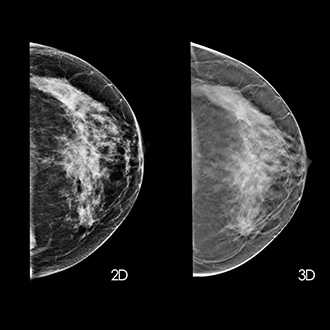

Mammography is important because in its earliest stages breast cancer may not be palpable; it may be too small to feel as a lump or tissue change. Mammography can help detect these changes two years or more before you would feel them. Physical examination is also important because premenopausal breast tissue is often dense and fibrous, which may decrease the reliability of mammography for young women.

Breast screening (mammography) is an X-ray examination of the breasts Breast screening can show breast cancer at an early stage, when they are too small for you or your doctor to see or feel

Breast screening can help find small changes in the best it shows up. Early detection of breast cancer offers the best chance of successful treatment, which significantly improves a woman’s chance of survival.